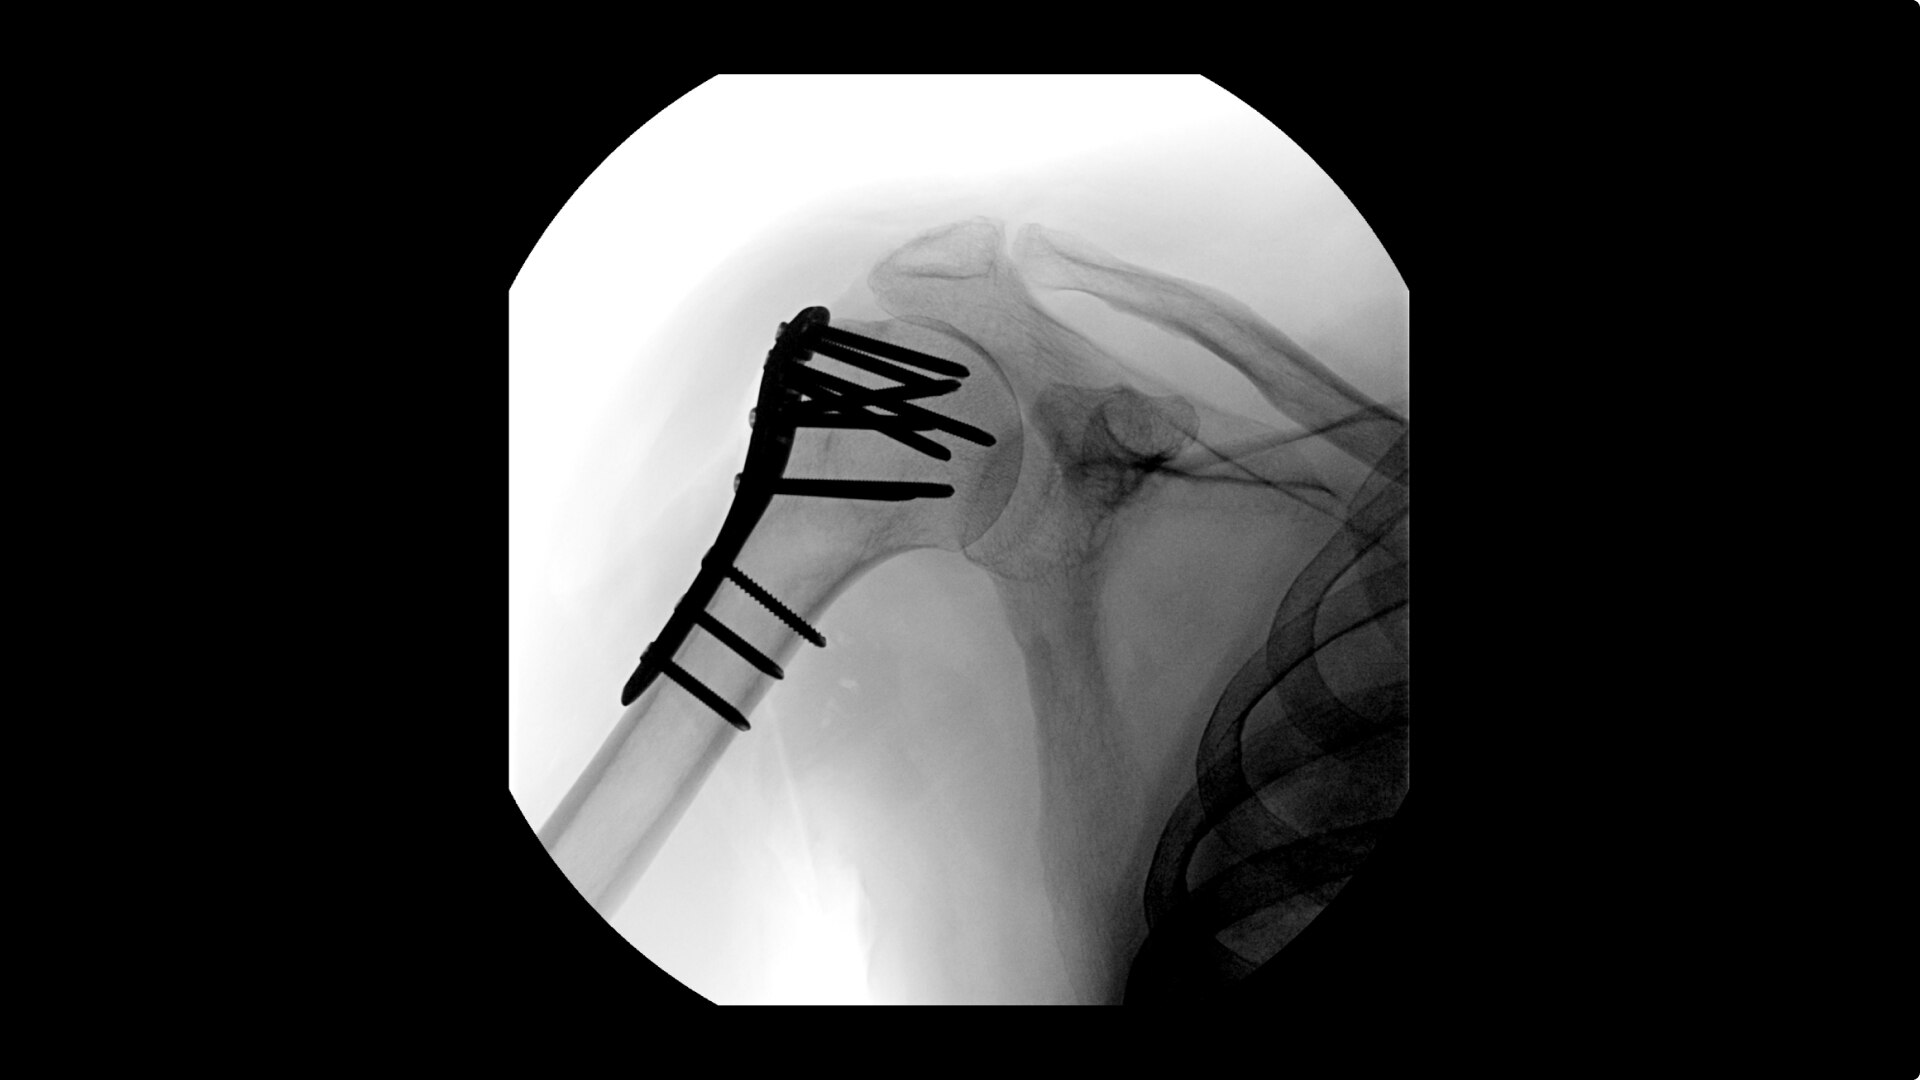

OEC C-arms provide orthopedic imaging with a large field of view optimized to clearly visualize orthopedic anatomy, such as the entire long bone femur or minute fractures in extremities. A clear display with comfortable viewing can easily show AP and lateral views, enabling efficient procedure planning.

Complex orthopedic procedures require powerful imaging systems. OEC premium C-arms perform in a variety of procedures such as:

• Humeral fracture

• Shoulder fracture reduction